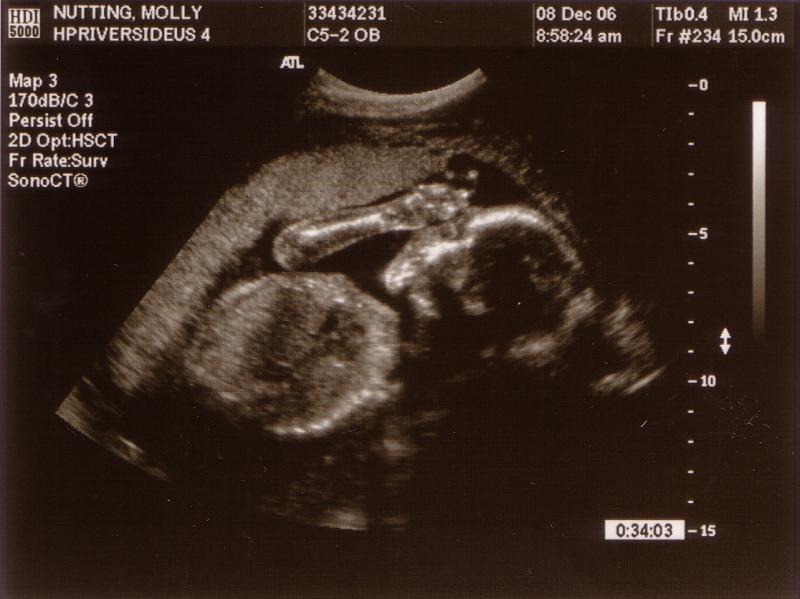

Foreshadowing

Ok, so this isn't a recent photo, clearly. Stephen and I were just going through these 21 week ultrasound photos, reminiscing. We now think this one is particularly interesting, because Nico was born with his hand right up next to his head, just like in this photo!